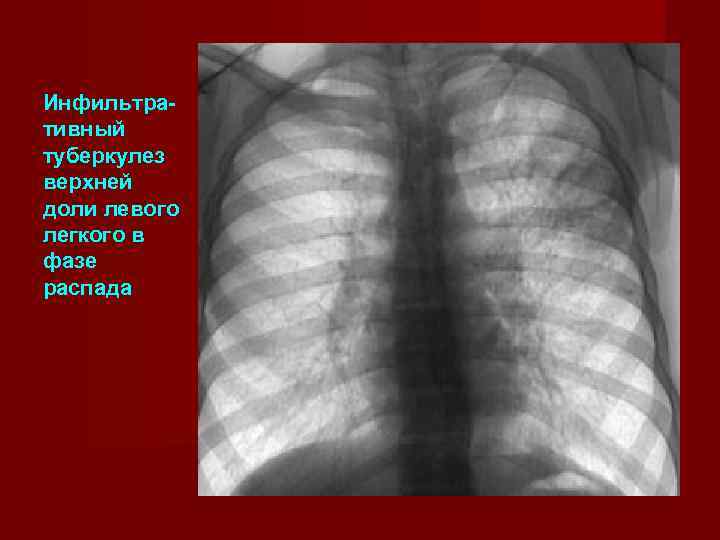

Иллюстрации по теме очагового и инфильтративного туберкулеза